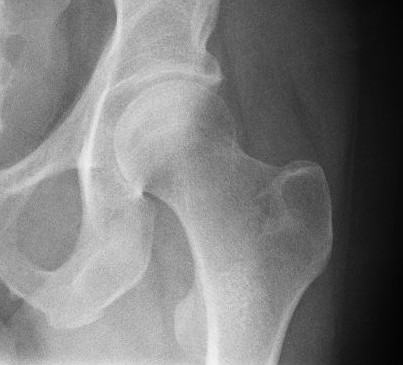

НЕОПЕРОВАНИЙ ПЕРЕЛОМ ЦІЄЇ КІСТКИ І В ЦЬОМУ МІСЦІ ПРИЗВЕДЕ ДО СМЕРТІ В СЕРЕДНЬОМУ ЧЕРЕЗ КІЛЬКА РОКІВ. А ЦІ РОКИ ПЕРЕТВОРЯТЬСЯ НА СИДЯЧІ АБО ЛЕЖАЧІ МУКИ. ЯКОЇ КІСТКИ І ЯКОЇ ЇЇ ЧАСТИНИ?

варіанти відповідей

HUMERUS, ХІРУРГІЧНА ШИЙКА

ВЕРХНЬОГО ДІАФІЗА

FEMUR, ШИЙКА

ULNA, ШИЙКА

ПРОКСИМАЛЬНОГО ЕПІФІЗА

ДИСТАЛЬНОГО ЕПІФІЗА

HUMERUS, ШИЙКА

RADIUS, ШИЙКА